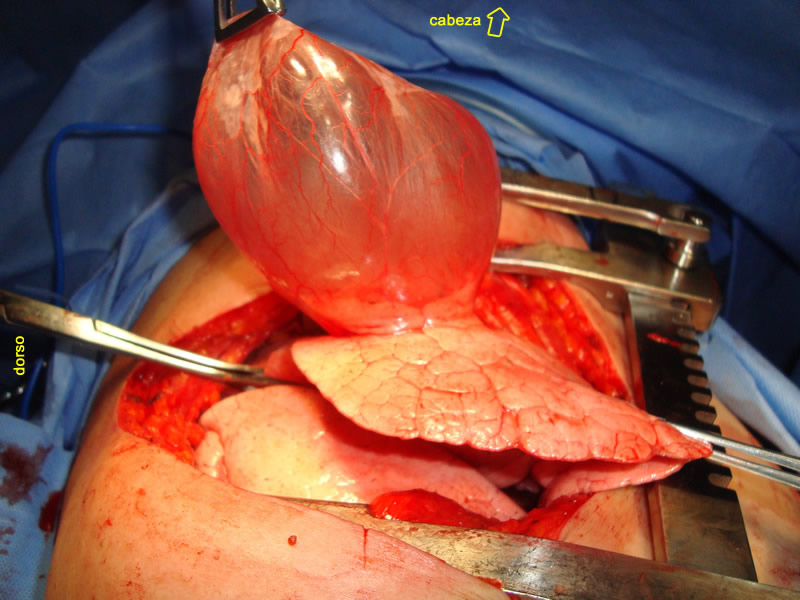

La exploración

mediante clasica toracotomia derecha, con conservacion del musculo serrato, a la altura del 5to.

arco costal, expuso un saco de aspecto traslucido y color rosado,

tenso, ocupando parte importante de la cavidad pleural,

emerge expontaneamente favorecido por la ventilacion positiva y estaba

localizado en el segmento lateral del lobulo pulmonar medio.

a-

bula enfisematosa, emerge espontaneamente por la incicion de toracotomia, favorecida su insuflacion

por la ventilacion mecanica

b-

lóbulo pulmonar superior derecho.

c-

lóbulo pulmonar inferior derecho.